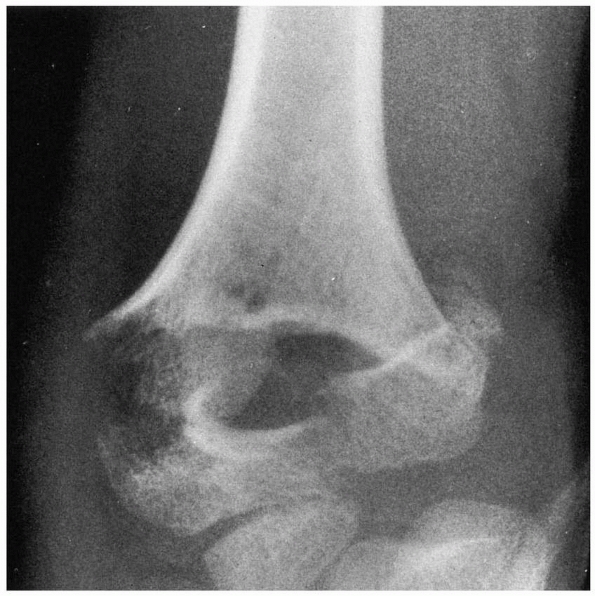

![]() |

FIGURE 15-13 Osteonecrosis of the lateral condyle after lateral condylar fracture in a 10-year-old boy. AP (A) and lateral (B) radiographs.

|